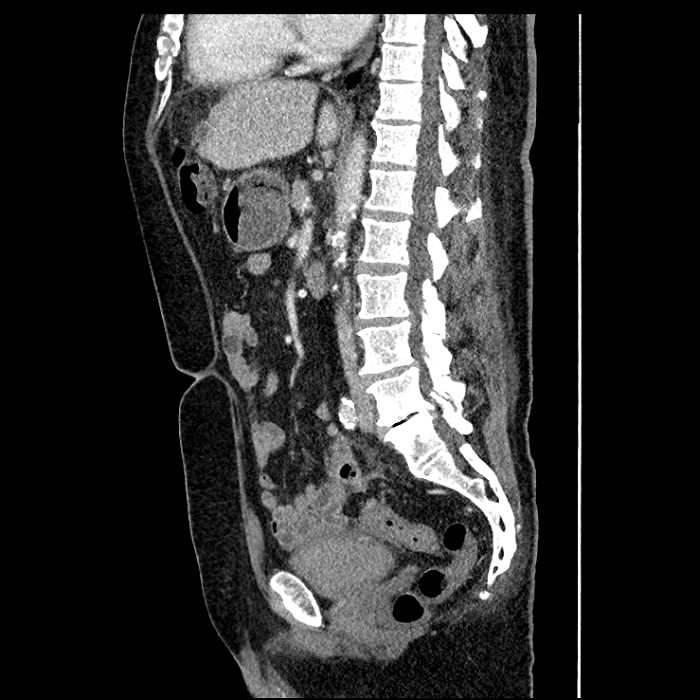

Age: 63

Sex: Male

Indication: Abdominal pain

Acute sigmoid diverticulitis complicated by a small contained perforation and a large abscess in the right hepatic lobe. Additional small subcapsular abscesses along the anterior margin of the left hepatic lobe.

Additionally, loss of the normal fat plane between the peridiverticular collection and adjacent thickened loops of small bowel raises the potential for an enterocolonic fistula.

High grade stenosis of the left common iliac artery. The left external and internal iliac arteries are patent.

Hepatic abscess showing the double target sign with low density internally surrounded by a thin inner enhancing rim (red arrow) and ill-defined outer low density rim (yellow arrow). Blue arrow indicates an internal septation. Red arrows: additional smaller subcapsular abscesses. Red arrow: focal contained perforation associated with diverticulitis.